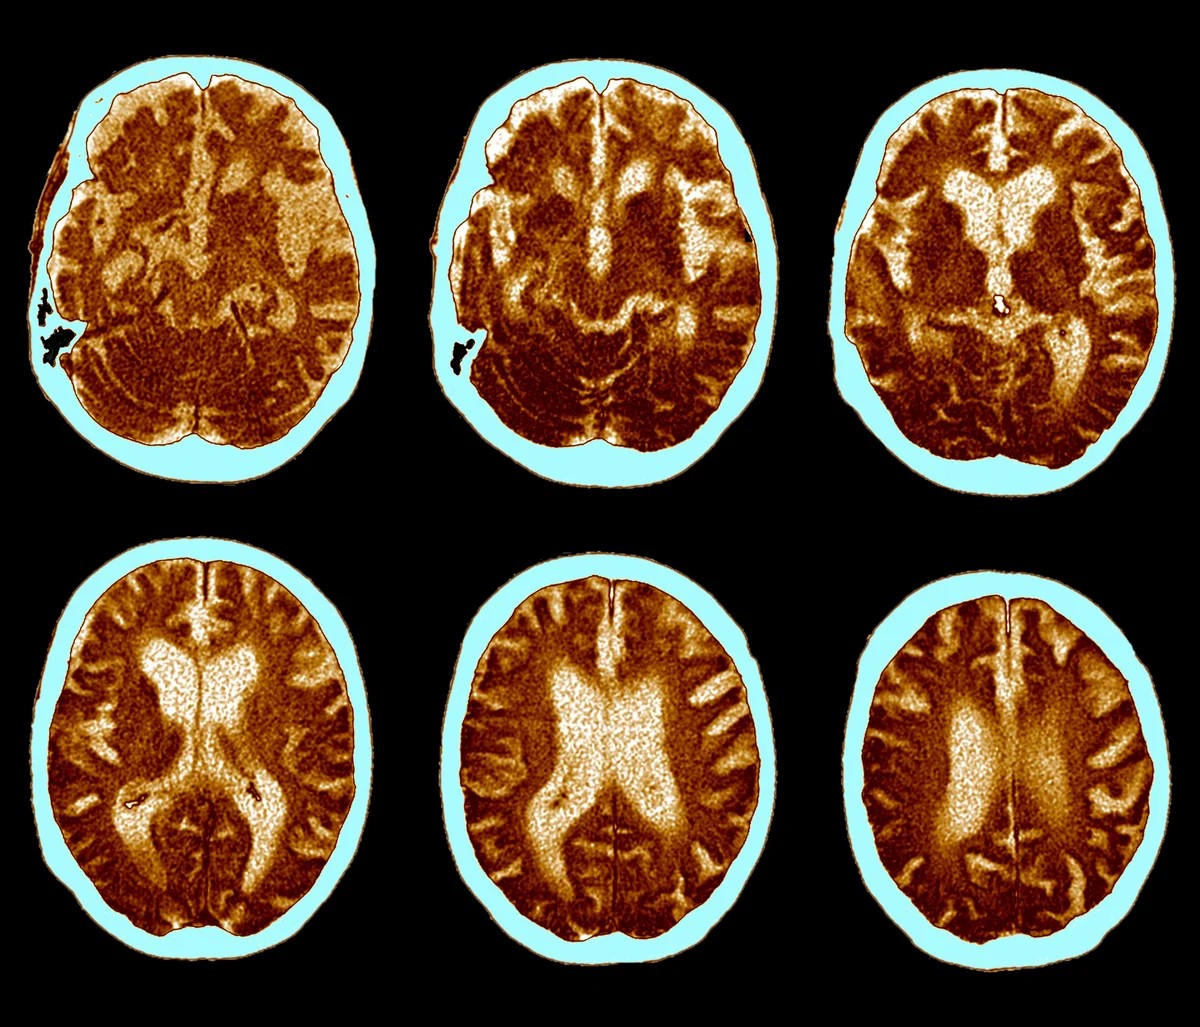

Два дослідження фази 3, які називаються evoke і evoke+, включали близько 4000 учасників віком від 55 до 85 років на ранніх стадіях хвороби Альцгеймера. Понад три роки половина учасників отримувала 14 мг перорального семаглутиду щодня, тоді як контрольна група отримувала плацебо. Хоча група, яка приймала препарат, помітила деякі покращення в біомаркерах хвороби Альцгеймера, препарат не зміг продемонструвати значного уповільнення когнітивного зниження. У результаті Novo Nordisk підтвердила, що припинить усі випробування семаглутиду для лікування хвороби Альцгеймера, включно з використанням ін’єкційної форми препарату.

Невдача перорального семаглутиду особливо помітна, враховуючи попередні дослідження, які свідчать про зв’язок між препаратами GLP-1 і зниженням ризику хвороби Альцгеймера. Дослідження на тваринах і дані спостережень вказують на захисний ефект, можливо, через протизапальні властивості цих препаратів. Вважається, що запальна реакція мозку прискорює прогресування хвороби Альцгеймера, а препарати GLP-1 продемонстрували здатність зменшувати запалення в інших частинах тіла.

Однак це дослідження показує, що лише системної протизапальної дії може бути недостатньо для впливу на прогресування захворювання. Той факт, що попередні позитивні результати в основному ґрунтувалися на ін’єкційному GLP-1, ставить питання про те, чи відрізнялися поглинання та розподіл пероральної форми в мозку.

За словами ендокринолога Деніела Друкера, який консультував Novo Nordisk, структура жирних кислот препарату могла перешкоджати його здатності долати гематоенцефалічний бар’єр і досягати критичних областей, таких як гіпокамп, який контролює пам’ять.